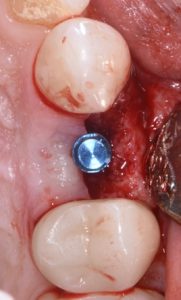

The case features flap management in the presence of a buccal dehiscence, followed by bone graft placement and stabilization using a dense polytetrafluoroethylene (d-PTFE) membrane. Surgical principles, membrane selection, and handling techniques are discussed to optimize ridge dimensions and facilitate future implant placement.

- Techniques for atraumatic extraction of endodontically treated teeth

- Flap design considerations in sites with buccal dehiscence

- Indications and advantages of d-PTFE membranes in ridge preservation

- Bone graft placement and membrane stabilization protocols